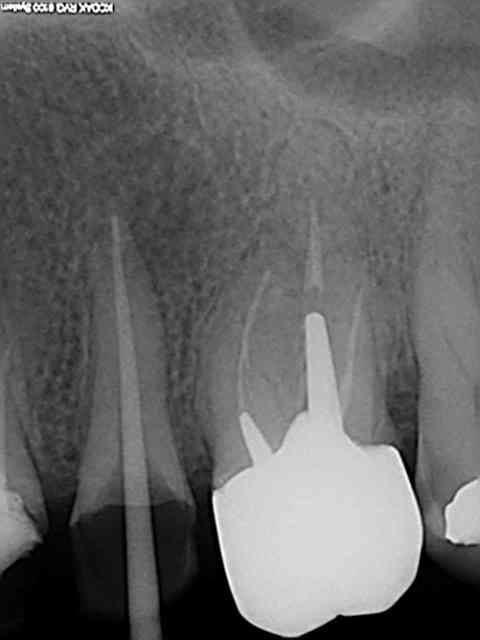

Monocone = minimum syndical vu le tarifs opposables de merde, je ne m'en cache pas, mais plus de lentulo. Des fois obturation au système B ou au mac spaden.

Apex défoncés, je ne comprend pas expliques. C'est vrai qu'il est plus simple de faire des endos à 4 mm de l'apex comme je vois souvent pour éviter de le leser je suppose.

Loin de moi l'idée de faire les meilleures endo du monde mais par contre je suis assez satisfait du résultat immédiat et à long terme, vu le minimum de temps passé à les faire (10 mn par canal en moyenne)

Tiens les endos de la semaine, que d'apex défoncés !-))

La 47 en fin le distal est obturé au système B (bouchon apical) et au mac spaden pour la partie coronaire, tu vois la différence à la radio ? Alors l'apex défoncé il faut avoir l'oeil ! peut etre mais à 25 centièmes et à conicité 6 %........-))